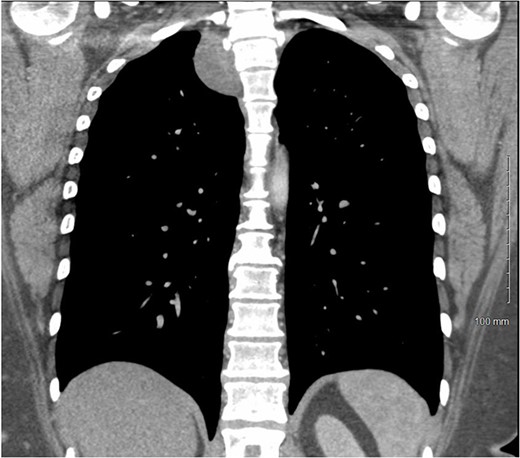

A 36-year-old female presented to an outside emergency department reporting chest pain, dizziness and abdominal pain for 7 hours. A computed tomography (CT) angiogram of the chest revealed a right paraspinal 4.2 × 2.8 × 3.3-cm cystic mass at the level of T2-3, which was well-circumscribed (Figs 1 and 2).

CT chest with IV contrast transverse view with detailed measurements of right T2-T3 paravertebral mass.